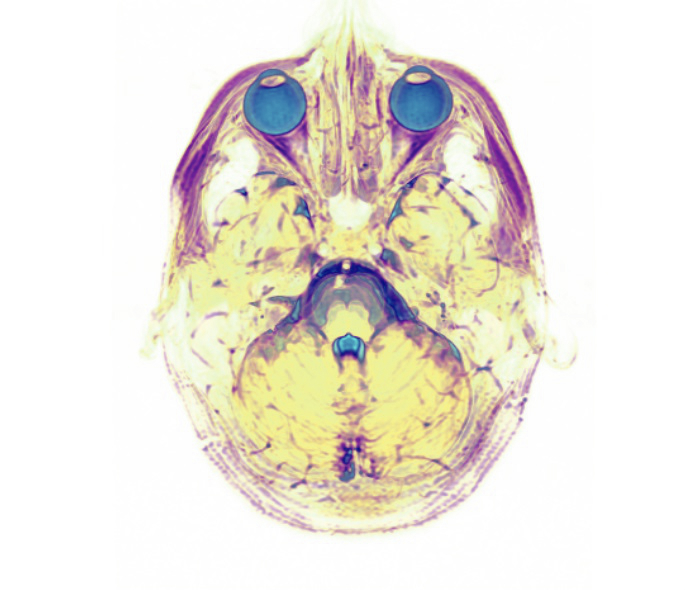

Millenium Magnetic Technologies (MMT) is the first company to commercialise the recording of resting state magnetic resonance imaging (MRI) scans, offering clients real-time stream of consciousness and dream recording.

Dr. Donald Marks, founder and chief science officer of MMT, claims that his patented Cognitive Engram technology can record detailed brain patterns and correlate them to thoughts and emotions for future interpretation.

"Some people call it 'thought identification' but it is essentially mind reading. It is the process of recognising activation patterns in the brain and identifying what thoughts are associated with them," Marks tells IBTimes UK.

Subsequent research found that through resting state MRI - which scans the brain without using a stimulus like a picture of a face - thoughts could be reconstructed from the data gathered.

Marks gives the example of someone thinking about a face. Currently, if someone thinks of a face while having their thoughts recorded, the image that is played back is "fuzzy", however Marks believes that over the next few years playback will improve much like the advancement of television.

"The visual reconstruction is kind of crude right now but the data is definitely there and it will get better. It's just a matter of refinement," Marks says. "That information is stored - once you've recorded that information it's there forever. In the future we'll be able to reconstruct the data we have now much better."

Reconstructed visual experiences from brain activity evoked after a subject watched a movie.University of California